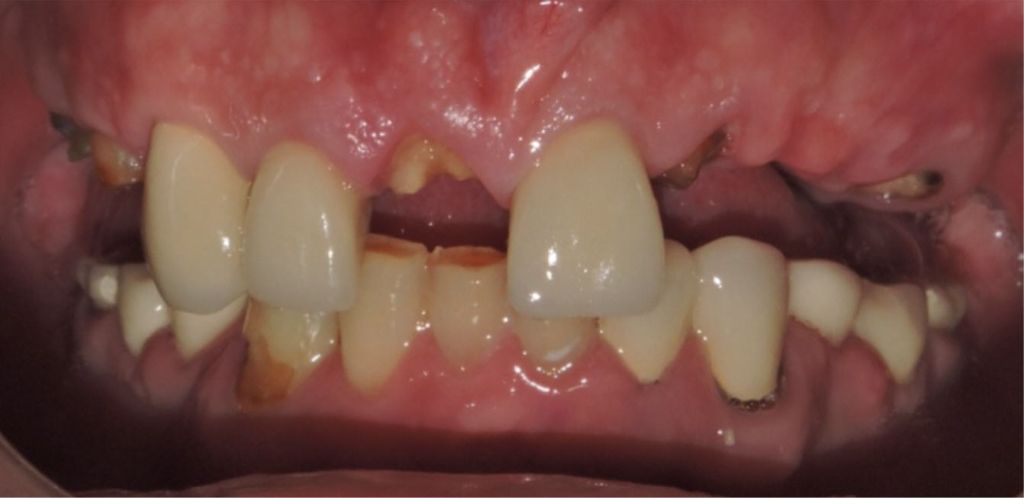

Before